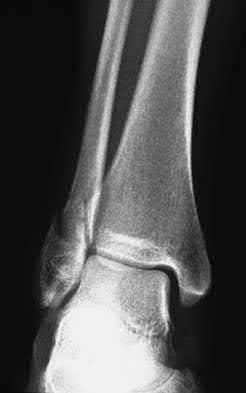

A 25-year-old female is involved in a motor vehicle collision. She presents with the isolated injury seen in Figures A through D. Her leg is swollen but her skin is intact. She has no clinical signs of compartment syndrome. Which of the following treatment options will allow for maintenance of fracture alignment and minimize the risk of soft tissue complications?

The patient presents with a closed distal third metaphyseal-diaphyseal distal tibia fracture with simple intra-articular extension. Immediate intramedullary nailing along with percutaneous fixation of the articular component provides appropriate restoration of length, rotation and alignment and minimizes the risk of wound complication.

Displaced distal third tibia fractures may be associated with simple intraarticular extension. Operative treatment of intra-articular distal tibia fractures has historically been performed with open reduction and internal fixation. Early open reduction and plate fixation of pilon fractures has been associated with high rates of infection and wound complication. In select patterns with simple articular extension, percutaneous screw fixation and medullary nailing may provide appropriate reduction with minimal soft-tissue risk.

Figures A and B demonstrate a distal third tibial shaft fracture with simple intra-articular extension. The axial and coronal CT cuts in Figures C and D further clarify the articular injury. Illustrations A and B demonstrate a comminuted distal third tibial fracture with simple intra-articular extension. Illustrations C and D are fluoroscopic images of the same injury after intramedullary nailing and percutaneous fixation of the articular component.